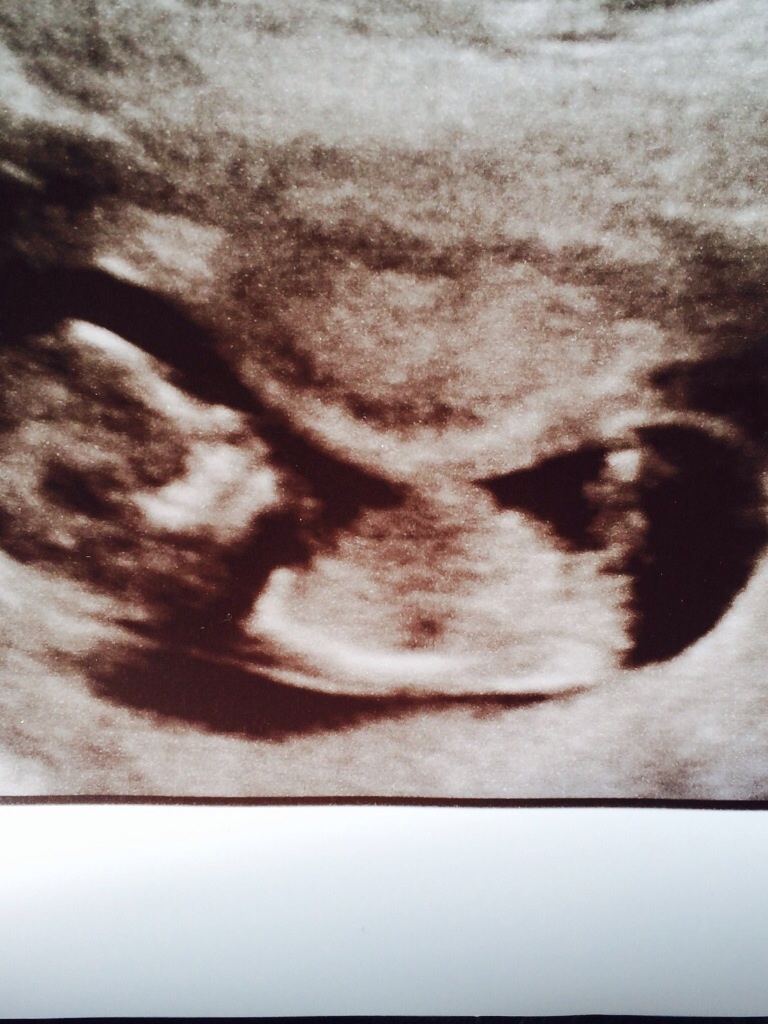

12 weeks 5 days

Attachment 19150Attachment 19150 here is a lighter closer version. Anymore guesses?

If what I'm looking at is the nub (I'm not 100% sure I'm looking in the right spot), it looks like a boy to me too.